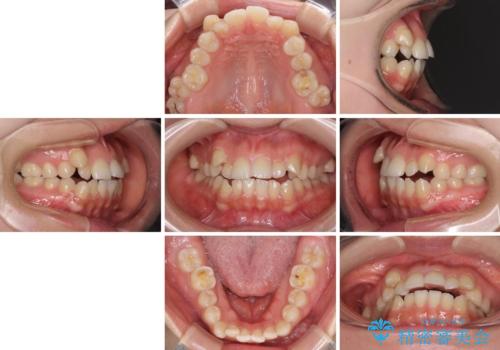

- 前歯のデコボコや八重歯、舌癖による開咬を気にして来院された患者様です。

目立たない装置を希望されたので、上顎が裏側装置のハーフリンガルを選択し、上顎小臼歯1本を抜歯して、補助装置を併用して矯正治療を行うこととしました。